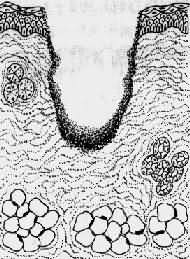

2.二期愈合(healing by second intention) 见于组织缺损较大、创缘不整、哆开、无法整齐对合,或伴有感染的伤口。这种伤口的愈合与一期愈合有以下不同:①由于坏死组织多,或由于感染,继续引起局部组织变性、坏死,炎症反应明显。只有等到感染被控制,坏死组织被清除以后,再生才能开始。②伤口大,伤口收缩明显,从伤口底部及边缘长出多量的肉芽组织将伤口填平。③愈合的时间较长,形成的瘢痕较大(图2-6)。

1.创口大,创缘不整,组织破坏多

2.伤口收缩,炎症反应重

3.肉芽组织从伤口底部及边缘将伤口填平,然后表皮再生

4.愈合后形成疤痕大

图2-6 创伤二期愈合模式图